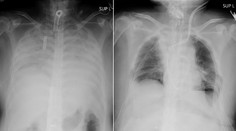

Zdravie Zjazvené pľúca a problémy s dýchaním. Fibrózu často odhalia až príliš neskoro Gabriela Šlebodová 29. 9. 2024

Lekári varujú pred tichým nepriateľom. Pľúcna fibróza môže mať ďaleko väčšie následky Gabriela Šlebodová 8. 9. 2025